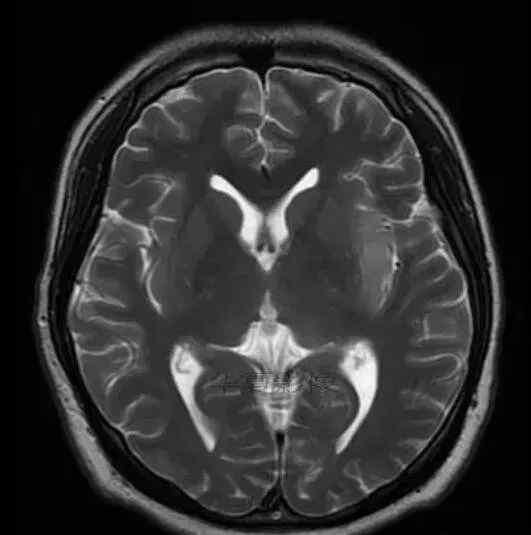

1.左侧颞叶、海马和岛叶T1WI信号低,T2WI信号高

2.病变没有明显的边界

3.占用效果不明显

4.豆状核不受影响